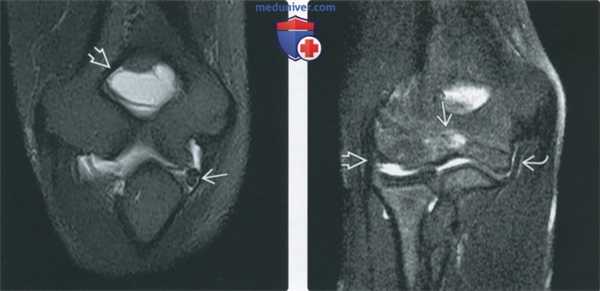

(Слева) МР-артрография в режиме Т1ВИ FS, коронарный срез: в заднемедиальном завороте локтевого сустава визуализируется свободное тело. Часто свободные тела выявляются еще и в завороте локтевого отростка.

(Справа) МР-артрография в режиме Т2ВИ FS, коронарный срез, подросток: визуализируется локальный отек костного мозга по краю зоны роста. ЛоКС и ЛуКС не изменены. Отек мог быть вызван хронической избыточной осевой нагрузкой, поскольку пациент занимался тяжелой атлетикой.